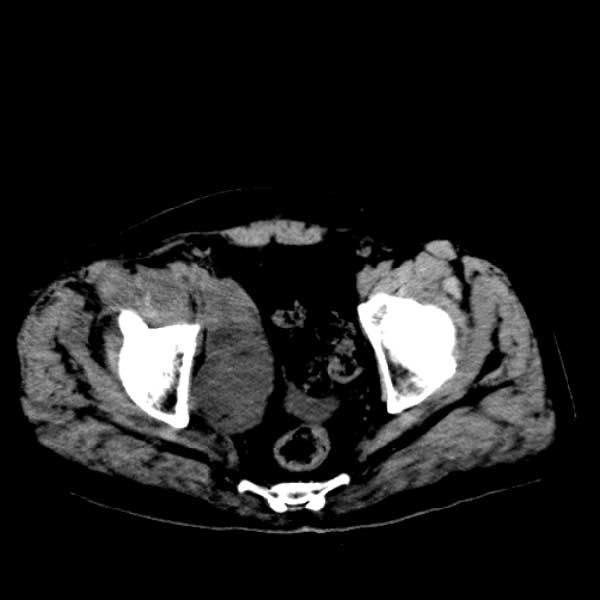

标题: CT13513:男 71 腹部疼痛20余天,近几天高热就诊,骨窗未见异 [打印本页]

标题: CT13513:男 71 腹部疼痛20余天,近几天高热就诊,骨窗未见异

考虑感染性病变可能性大,起源于阑尾?

考虑为化脓性阑尾炎.脓肿形成.及多肌肉累及.

考虑右侧腰大肌脓肿,向右髂窝、右腹股沟流注。

支持化脓性阑尾炎伴右髂窝脓肿、腰大肌腰方肌脓肿形成。

考虑腹腔及盆腔化脓性炎症,累及右侧髋关节及腹股沟区.

首先考虑化脓性阑尾炎伴腰大肌、腰方肌脓肿,不除外回盲部结核。

回盲部癌待排除。

患者肠镜检查考虑结肠癌,病理证实

患者肠镜检查考虑结肠癌,病理证实。肺部ct可见多发结节,考虑转移